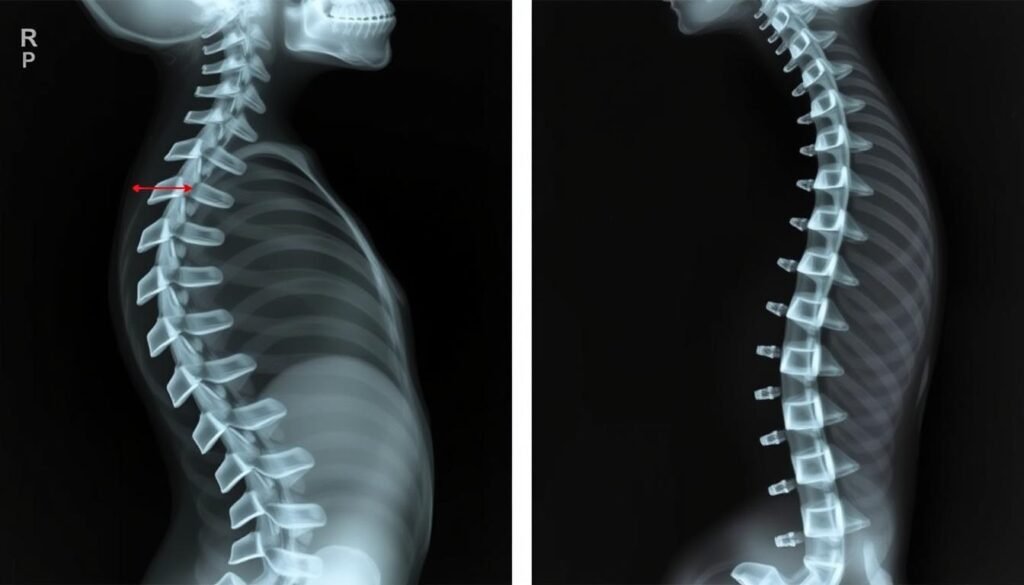

Vergleich zwischen einer gesunden Wirbelsäule und einer Wirbelsäule mit Skoliose

Eine Skoliose ist eine komplexe dreidimensionale Verformung der Wirbelsäule. Während eine gesunde Wirbelsäule von hinten betrachtet gerade verläuft, zeigt sich bei einer Skoliose eine seitliche Verkrümmung. Zusätzlich kommt es zu einer Rotation der Wirbelkörper, wodurch sich diese um ihre eigene Achse drehen. Diese Verdrehung führt oft zu einem sichtbaren Rippenbuckel, wenn sich die Betroffenen nach vorne beugen.

Medizinisch spricht man von einer Skoliose, wenn der sogenannte Cobb-Winkel mehr als 10 Grad beträgt. Dieser Winkel wird mittels Röntgenaufnahmen bestimmt und gibt Auskunft über den Schweregrad der Verkrümmung. Je nach Ausprägung unterscheidet man zwischen:

Röntgenbild mit Messung des Cobb-Winkels zur Bestimmung des Skoliose-Grades

- Röntgenaufnahme: Standardverfahren zur Bestimmung des Cobb-Winkels und der Skelettreife

Röntgenaufnahme vor und nach operativer Skoliose-Korrektur